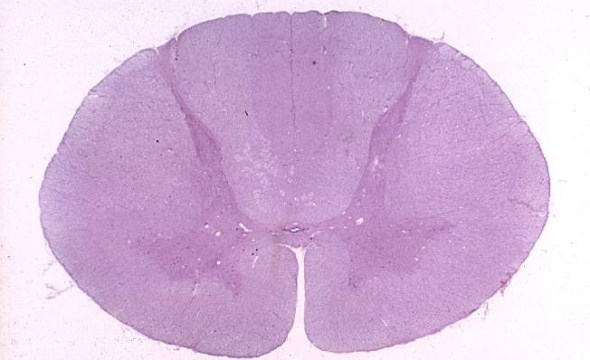

Know your spinal cord – The landmarks

A human cervical spinal cord slice. Once you’ve read this post, you should be able to identify the major parts and tell which side is the front of the cord.

Welcome to day thirty-three in our series. For those of you who are just finding us, we have every one of these posts in our neuroanatomy category in reverse chronological order. Today we’re going to backtract (get it?) a little and go over something basic, but something we’ve skipped over to this point. We never really talked about the landmarks of a spinal cord slice. So today, we are going to take a detour and go over spinal cord features.